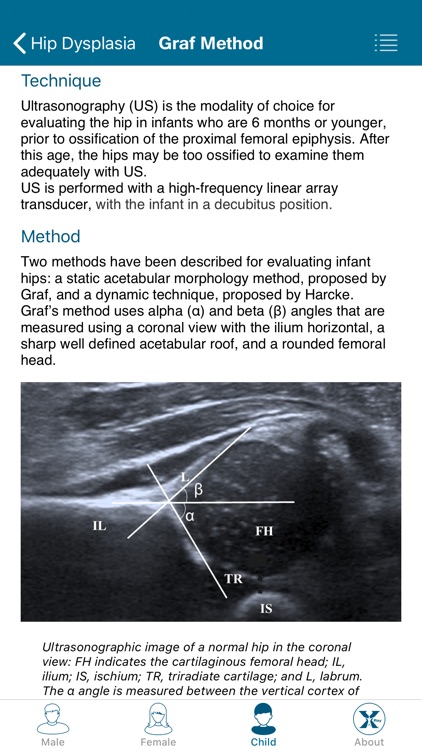

Created by radiologists for all those who practice medical imaging, this application constitutes an atlas of the main measurements in radiology and their normal values based on the most cited literature. It illustrates easy and reproducible methods using different imaging methods.

Created by radiologists for all those who practice medical imaging, this application constitutes an atlas of the main measurements in radiology and their normal values based on the most cited literature. It illustrates easy and reproducible methods using different imaging methods.

The application covers multiple imaging modalities: radiography, ultrasound, CT and MRI. The modules are divided into six sub-specialties: osteoarticular, cervical region, thorax, cardiovascular, abdomen and pelvis.